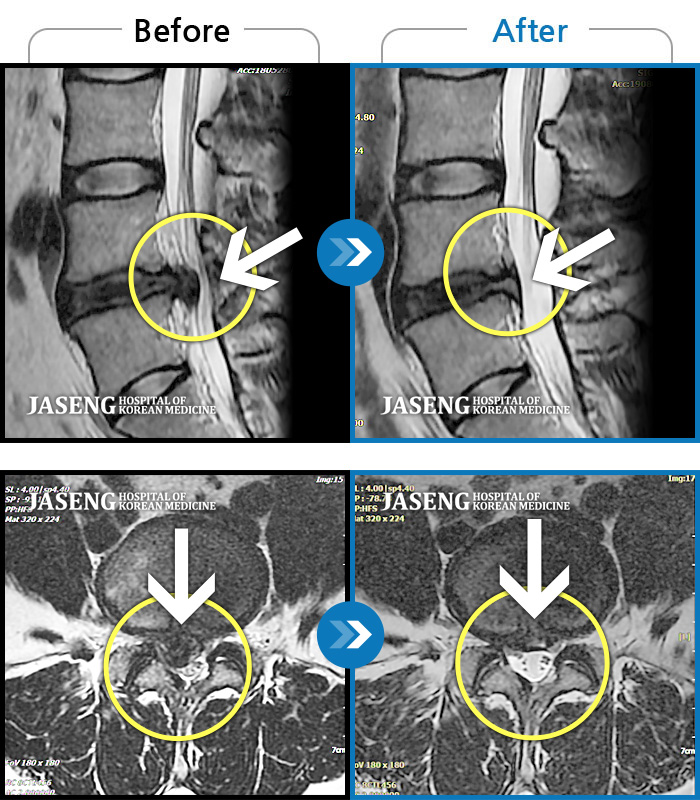

Before

After

환자에게 사전 동의를 받아 동일 조건에서 촬영되었습니다.

개인에 따라 치료 후 부작용이 발생할 수 있으니 의료진과 상담 후 치료를 진행하시기 바랍니다.

허리와 좌측 골반 통증, 좌측 다리에 통증 및 근력, 감각 저하

좌측 허리와 골반에 통증, 좌측 다리에 통증과 저림